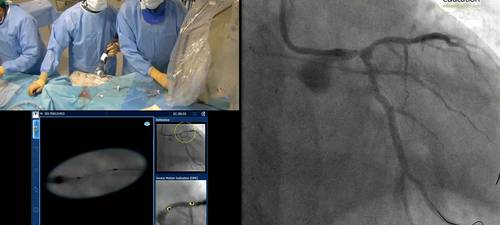

Prof Javier Escaned provides a live case transmission from Clinico San Carlos, Madrid, Spain.

• Live case demonstrations using IVUS co-registration

Learning core IVUS skills – three cases illustrating the most important things a new IVUS user must be able to recognise - Prof Javier Escaned

Live case transmission from Clinico San Carlos, Madrid, Spain